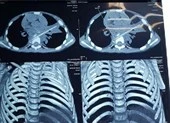

Sáng 22-3, BS Đinh Trọng Toàn - Khoa Chẩn đoán hình ảnh, BV quận 11, TP.HCM cho biết BV này vừa thực hiện nội soi lấy dị vật thực quản cho bệnh nhân NTTV (sinh năm 1993, quê Tiền Giang).

Trước đó, vào lúc 13 giờ ngày 11-3, bệnh nhân V. được đưa vào khoa Ngoại Tổng quát - BV quận 11 do đã cắn và nuốt 1/3 que xiên thịt nướng. Thế nhưng khi các bác sĩ thực hiện nội soi thực quản - dạ dày - tá tràng cho chị V. lại không thấy dị vật ở vùng hầu họng do dị vật đã di chuyển xuống ruột non. Bệnh nhân được chỉ định thực hiện nội soi lấy tăm xiên que ra khỏi thực quản.

Bệnh nhân đang được nội soi lấy que thịt nướng ra khỏi ruột non. Ảnh: BVCC